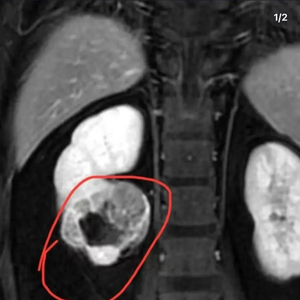

近两年,一种装在透明袋子里的“捏捏”,成为年轻人缓解压力的热门选择。近日,一位ID名为“有只猫叫小朋友”的捏捏博主发文告诉粉丝:“得癌了,近期都不会更新捏捏了。”博主公开了自己的诊断病例,显示诊断意见为“右肾下级占位,肾CA可能,建议穿刺活检。”意味着医院给出的诊断是右肾下极区域出现异常组织占据,存在肾细胞癌的可能,让解压玩具捏捏致病问题,再度成为热议话题。